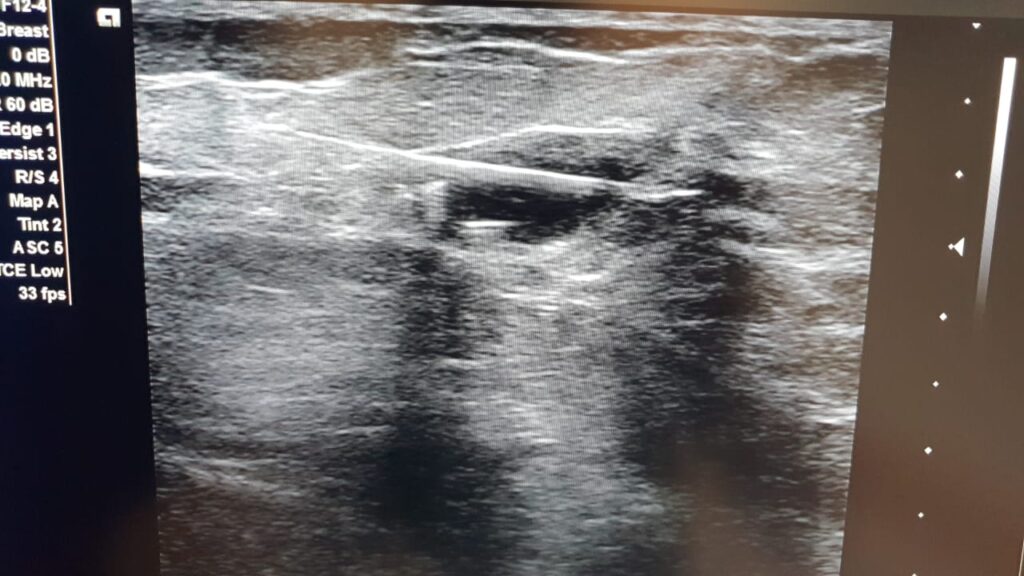

Breast Wire Localization Placement

Expert breast wire localization and precision-guided care services available at NIRS.

Breast Tumor Marker Clip Placement

Expert breast tumor marker clip placement and precision-guided breast care services available at NIRS.